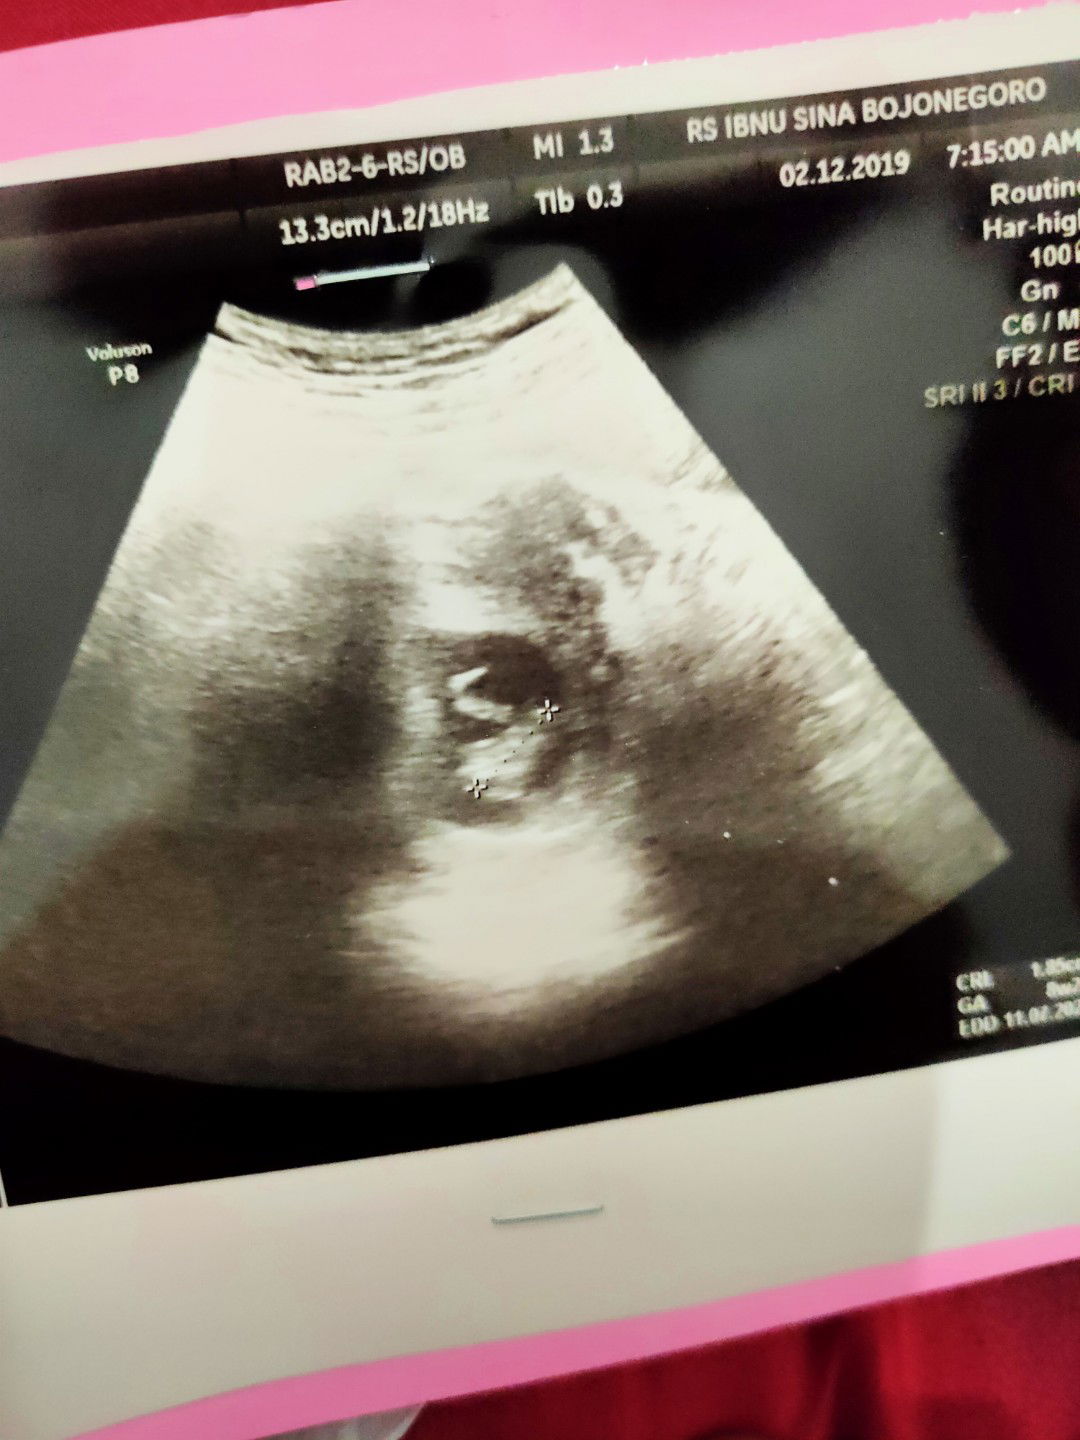

ukuran janin

Bun, aku usg uk 8w .. apa memang bentuknya seperti itu ya bun .. ??